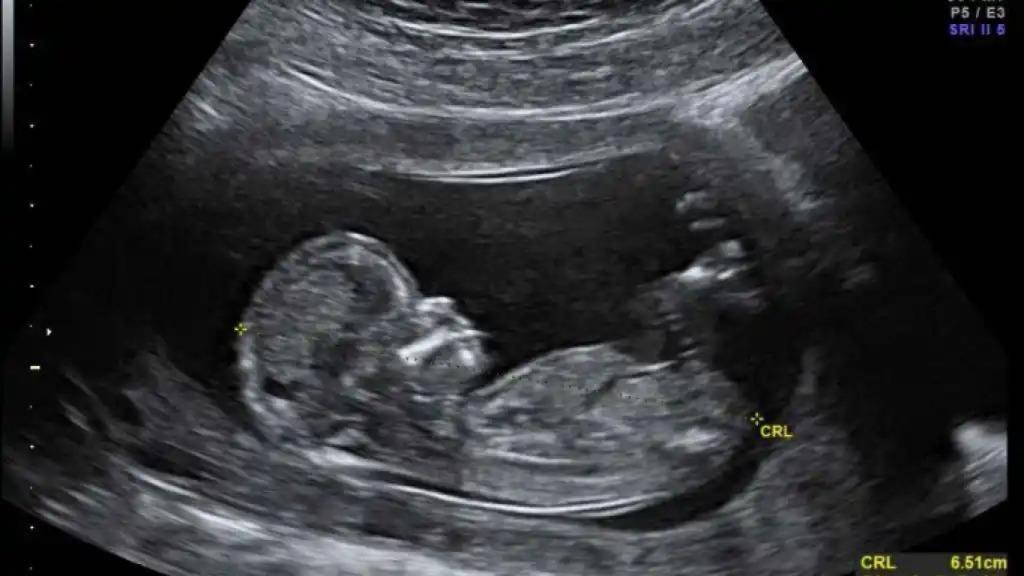

La madre tomaba el medicamento que le llegaba al feto a través de la placenta.

Así que la madre comenzó a tomar risdiplam —tiene un coste de alrededor de 300.000 euros anuales pero el laboratorio que lo fabrica lo ofreció de forma gratuita con fines de investigación— desde la semana 32 del embarazo hasta la 38, cuando dio a luz.

Las pruebas de líquido amniótico y sangre umbilical mostraban que el fármaco estaba llegando al útero y pasando al feto. El bebé mostraba un aumento de los niveles de la proteína SMN.